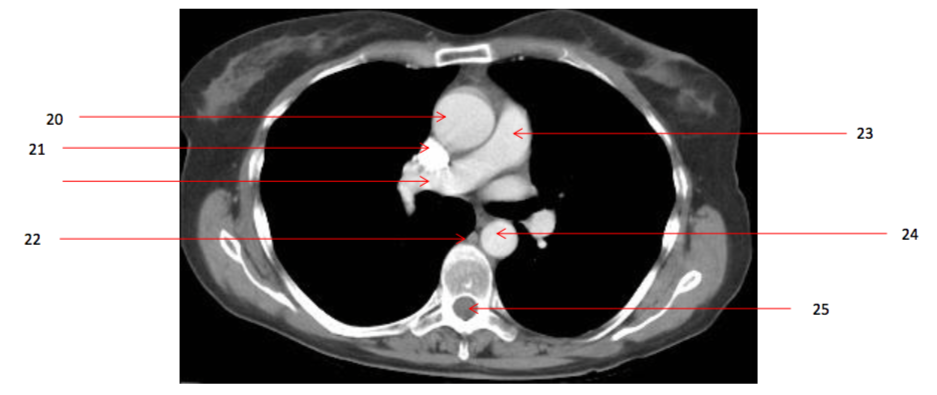

Q

Ascending aorta

Number 22?

Number 29?

Azygos vein

Number 27?

SVC

Number 31?

Ascending aorta/aortic valve

Number 28?

Rt pulmonary vein

Number 24?

Descending thoracic aorta